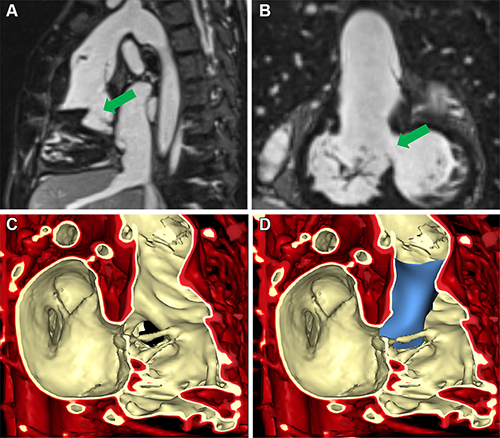

Figure 2. Volume rendering of ferumoxytol-enhanced inversion-recovery fast low-angle shot imaging from cardiac MRI in a 6-year-old female patient with a right ventricle to aorta and malalignment ventricular septal defect (VSD) (patient 2) to inform planning of biventricular repair. (A) Sagittal and (B) coronal views demonstrate VSD (green arrow). (C) Volume rendering of cardiac MRI. (D) Volume rendering with baffle placement using SlicerHeart.